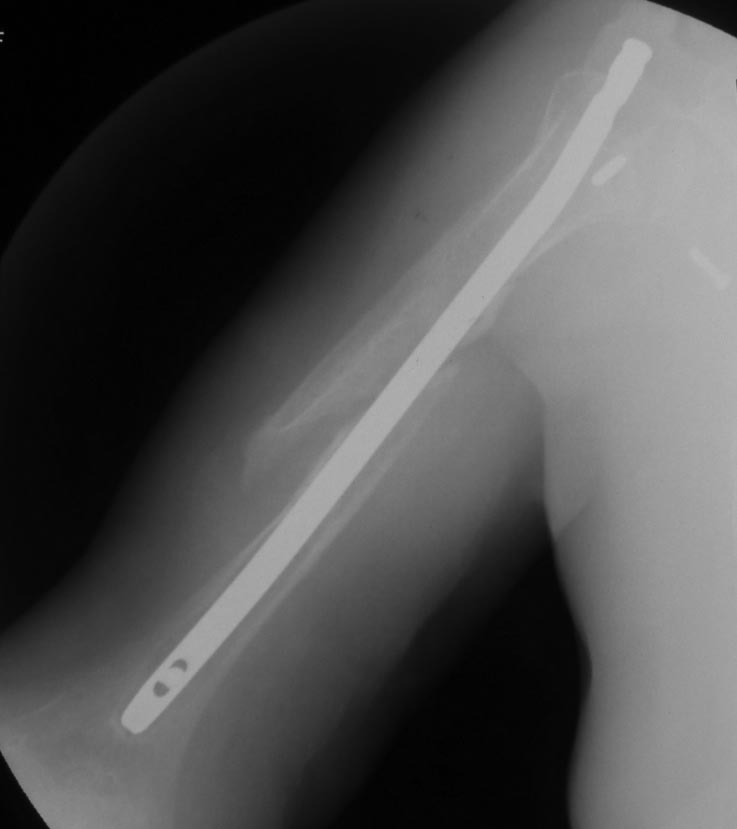

Уважаемые коллеги! Пациент получил травму около 1 года назад, выполнялся остеосинтез по поводу переломов лучевой, бедренной, плечевой костей. Обратился в связи с выраженной контрактурой в коленном суставе (сгибание 10-15 град)и практически отсуствием самостоятельного отведения плеча. Снимки представлены. Планируем выполнить реостеосинтез плеча (скорее всего этим же стержнем, так как другого нет) с коррекцией положения отломков в проксимальном отделе и сближением отломков в области диафиза. По надколеннику пока одна идея - его удаление. Хотелось бы услышать мнение и советы участников форума. - необходима ли будет костная пластика в области диафиза плеча? - адекватен ли по Вашему мнению реостеосинтез стержнем? - какая тактика в отношении ротационной манжеты? - приведет ли удаление надколенника и релиз сустава к существенному улучшению функции? Спасибо.

Надколенник-то, когда сломался? Не при редрессации-ли? Синтез плеча изначально сделан сикось-накось, надо переделывать, стержень - слишком длинный (видно вбили что есть), его использовать не удастся. То место, откуда торчит проксимальный конец стержня с винтами к вращательной манжете отношения не имеет - это немного выше, у бугорков. А что за радикализм в отношении надколенника? Удивляет то, что это пока единственная идея, пришедшая в голову автора;). Надо делать синтез, при этом и осуществить артролиз, а дальше видно будет.

2. На счет длины стержня не согласен. если ввести его в типичной точке будет как раз.

Снимки бы почетче в обеих проекциях увидеть, и на всем протяжении - пока одна мутная проекция, дистального конца ни стержня, ни плечевой кости нет. Функциональные снимки делали, в максимальном отведении? Дефицит отведения только за счет варусной деформации, то есть проксимальный отдел плеча отводится нормально?

Насчет реостеосинтеза можно позже подумать, когда хорошие рентгенограммы будут.

- удаление железа,

- в дистальной части реостеосинтез пластиной с костной пластикой,